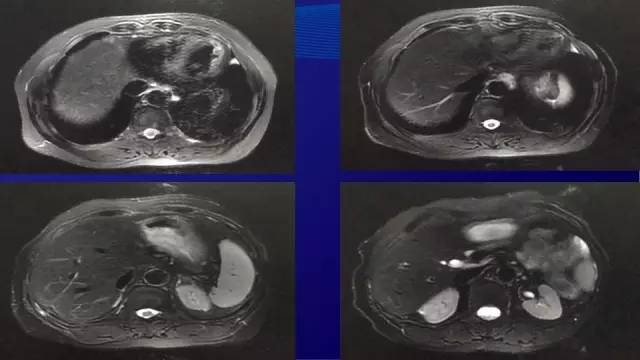

● 2015.07行肝转移灶切除术

● 术中见肝II, III段7*6*4厘米质硬灰白色结节,VI段6*5*7厘米质硬灰白色结节,切除肝II,III(2枚)和VI段的肿物(2枚)

● 术后病理:(肝)中分化腺癌,免疫组化符合肠癌肝转移。其中2枚消融病灶坏死成分约80-90%;另两枚病灶坏死成分约30-40%,纤维化约20%。

● 随访23个月无瘤生存